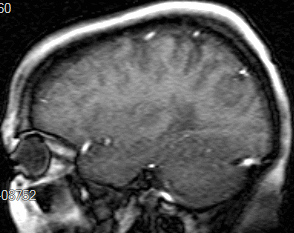

A csigolyaszámoló kurzorral címkézheti a csigolyákat és a csigolyaközöket. Ezek az előre meghatározott címkék saját megfelelő helyükön jelennek meg a képeken minden ortogonális síkban.

Csigolyaszámolás beillesztéséhez:

A jobb egérgombbal a képernyőre kattintva megjelenik a csigolyaszámolás vezérlőpanelje. Ez a mező lehetővé teszi a felhasználó számára a csigolyák és csigolyaközök címkézésének visszaállítását, és új szintek kiválasztását.

Axiális, coronális, szagittális |

A csigolyaszámolások minden képen megjelennek a relatív síkban. A kép annotálásának időpontjában érvényes. |

Alkalmazott sík |

A címkéket ugyanabban a síkban jeleníti meg a képeken, mint a gerinc annotálásához használt sík. |

A megadott címkék ortogonális képeken való elhelyezéséhez az ábrának a fókuszponttól meghatározott távolságban kell metszenie a képet, amely ezután megjelenik a metszési síkban. A csigolyaszámolások automatikusan megjelennek az összes ortogonális képen. Ha a referenciakocka nincs előre meghatározva, a képeket egyenként kell címkézni. Ha a fókuszpont a megadott távolságon kívül esik, nem jelenik meg címke.